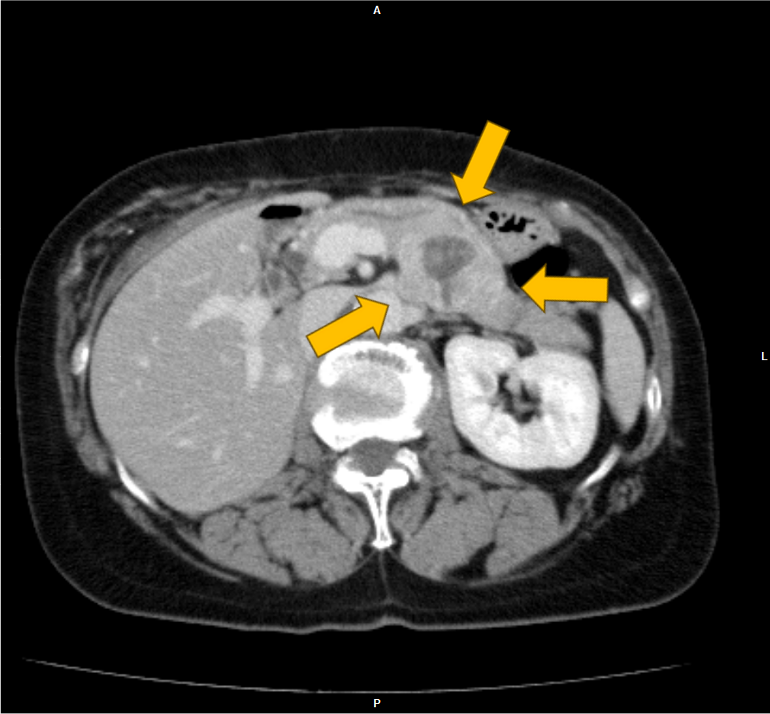

右腎癌(淡明細胞型腎細胞癌)術後の経過観察中に、左腎、膵尾部、胸骨の腫瘍が明らかとなり、胸骨病変の組織診断により右腎癌の転移の確定診断となった。本CTは化学療法中の治療効果判定目的に施行された腎ダイナミック造影CTである。

当該疾患の診断における造影CTの役割

右腎癌術後(淡明細胞型腎細胞癌)、左腎、膵体部、胸骨背側に腫瘤を認める。造影CTにおいての膵実質との増強効果の違いにより膵腫瘍を描出することができる。膵腫瘤はDynamic造影で早期濃染色、washoutパターンを呈しており、乏血性の造影パターンを呈す通常の膵癌との鑑別は容易である。